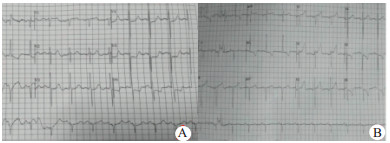

患者于当日23:50送达本院急诊抢救室。来院时神志不清,GCS评分7分,血压132/87 mmHg(1 mmHg=0.133 kPa),心率90次/min,呼吸22次/min,脉搏92次/min,血氧饱和度96%,血糖6.7 mmol/L。查体见面色红润,舌体咬破。两肺呼吸音清,未闻及干湿性啰音,心律齐,无明显病理性杂音,腹平软,压痛反跳痛难以配合,两侧病理征未引出。2019-01-02 23:58心电图示窦性心律,ST段改变(图 1A)。2 h后复查心电图示窦性心动过缓,ST-T改变,左室高电压、心电轴左偏,Ⅰ、Ⅴ5、Ⅴ6导联ST段呈水平型、下斜型压低,0.05~0.1 mV,Ⅴ1、Ⅴ2、AVR呈水平型抬高(图 1B)。(2019-01-03 00:15)床边检测cTnT 0.014 ng/mL,D-二聚体 > 10 000 ng/mL,NT-pro BNP 20 600 ng/L。2 h后复查cTnI 0.049 ng/mL。生化示肌酐284 μmol/L,其余指标未见明显异常。头颅CT示右侧颞枕叶条片灶,局部似与右侧脑室后角相连,脑裂畸形:合并灰质异位?软化灶合并脑穿通畸形?(图 2)。胸部CT示心脏增大、肺动脉高压,肺动脉主干增宽4.0 cm,心包前部少许积液。床边心超示:左室壁运动欠协调,室间隔运动稍减弱,主动脉瓣反流(轻度),EF为52%。患者入院后烦躁不安,先后予镇静、抗癫痫等治疗。因患者D-二聚体升高明显,胸部CT示肺动脉增宽明显、肺动脉高压,考虑存在肺栓塞可能; 另一方面,患者血压呈进行性上升,D-二聚体升高,CT示心包前部少许积液,故主动脉夹层亦不能除外,需行动脉造影明确,但因患者肌酐异常,存在慢性肾衰竭,行增强CT检查需注射造影剂,可能进一步加重肾损害,故家属拒绝。2019-01-03 07:00患者神志转清,诉有头晕,无胸痛,血压持续波动在200/100 mmHg左右,予镇静、降压效果均较差,病情反复告知家属,家属商议后最终同意行CTA检查。13:05行胸部增强+肺CTA示主动脉弓夹层(De Bakey I、Stanford A型),肺动脉高压(图 3)。最终患者诊断主动脉夹层(De Bakey I、Stanford A型)明确,因本院手术条件所限,当天即予转上一级医院手术治疗。

| 图 1 A:患者入院时的心电图; B:患者入院2 h后的心电图 |